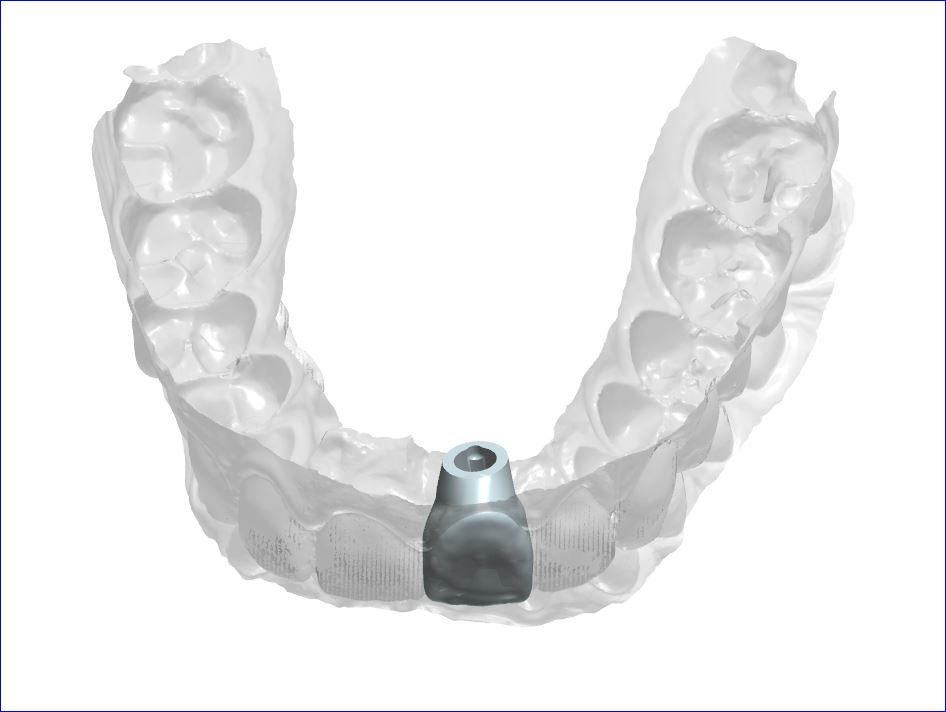

Replacement of failing lower back teeth

Immediate implant molar replacement involves placing a dental implant directly after tooth extraction in a single, minimally invasive procedure. This technique reduces healing time and preserves jawbone structure. It’s ideal for patients seeking swift treatment without extensive surgical intervention, enhancing overall dental care efficiency.

CAD/CAM dentistry uses digital technology for precise, efficient design and manufacturing of dental restorations, offering quicker turnaround and enhanced accuracy compared to conventional methods, which rely on manual impressions and techniques.

POSTERIOR IMPLANT

This patient came to see Dr. Andrews in our Boston Dental Practice with the desire to replace her missing lower left molar (#19). Since the extraction was done more than a year prior to the visit, more than 50% of the bone volume was lost. Being the second biggest tooth in the mouth, a lower molar requires a strong foundation to be built on.

Studies confirmed, that for long-term success, an implant diameter for such case should be no less than 5 mm. With only 3 mm width of the bone available here, no implant can be placed without a bone graft. The classic (old) treatment planning dictates the two-stage approach. The bone graft (ridge augmentation) is done first. After 4-5 months, when the bony ridge is wide enough (10-12 mm), an implant is placed. Then another 5-6 months are required for the implant to integrate with the bone. Add another month to make a crown. Thus, the total treatment time is 10-12 months.

Using modern, advanced surgical techniques, combined with PRF protocol, Dr. Andrews was able to combine bone graft with the simultaneous implant placement. He augmented the bone ridge wide enough to place 7 mm implant diameter. That is 200% more implant-to-bone surface area compared to a 5 mm one. Such a strong foundation should be able to support the implant crown for the entire patient’s life. This case took Dr. Andrews 5 months to complete, with only one surgery.